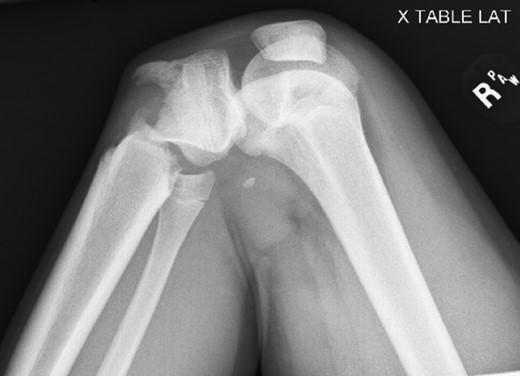

Patient is a 14-year-old male who slipped and fell while jumping off of a diving board and landed onto a flexed right knee. The patient was stable on presentation and neurovascularly intact with the knee locked in flexion. Skin was tenting anteriorly over the tibial tubercle and his compartments were swollen but compressible. A single plain film view (Fig. 1) was obtained prior to orthopaedic consultation. Closed reduction under sedation and splitting was attempted in the ED with partial but unsatisfactory improvement. Post-reduction radiographs (Fig. 2) demonstrated a tibial tubercle fracture with extension through the entire proximal tibial physis with metaphyseal involvement posteromedially. We classified this as a type IV tibial tubercle fracture, Salter–Harris II variant. In conjunction with patient and family we planned for urgent closed versus open reduction and application of knee-spanning external fixator. Immediately prior to surgery in the pre-operative holding area, the patient noted increasing right leg pain. In the operating room (OR), a marked increase in swelling with tense skin was observed. Due to rapidly progressive swelling and nature of the fracture, the decision was made to proceed with a 4-compartment fasciotomy of the right leg. The medial-sided fasciotomy (Fig. 3) revealed significant bulging of the superficial and deep compartments; however, the anterior and lateral compartments were less swollen. The fracture was unable to be closed reduced intraoperatively, therefore proximal extension of the medial fasciotomy wound was performed to open and reduce the fracture under direct visualization. Anatomic reduction was achieved and a knee-spanning external fixator was applied (Fig. 4). Approximately 72 hours later the patient was brought back to the OR for irrigation and debridement, lateral wound closure, and medial wound vacuum placement. Another 72 hours later, he returned to the OR for removal of the external fixator, ORIF, and split-thickness skin grafting of the medial fasciotomy site. An anterolateral approach was used with a 3.5 mm proximal tibial locking plate (Fig. 5). At most recent follow-up (Fig. 6), six months post-op, the patient is pain free, ambulating without assistive device, and has returned to all desired activities.

Presenting plain film view demonstrating proximal tibia fracture.